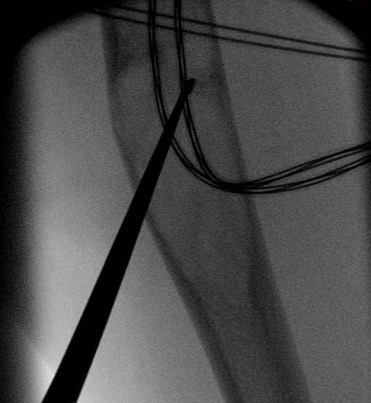

Surgical cyst drainage using implants

Concept

- venous hypertension cause of cyst

- if allow cyst to drain, will heal

Options

- cannulated screws in calcaneum

- flexible nails humerus

- intramedullary nail femur